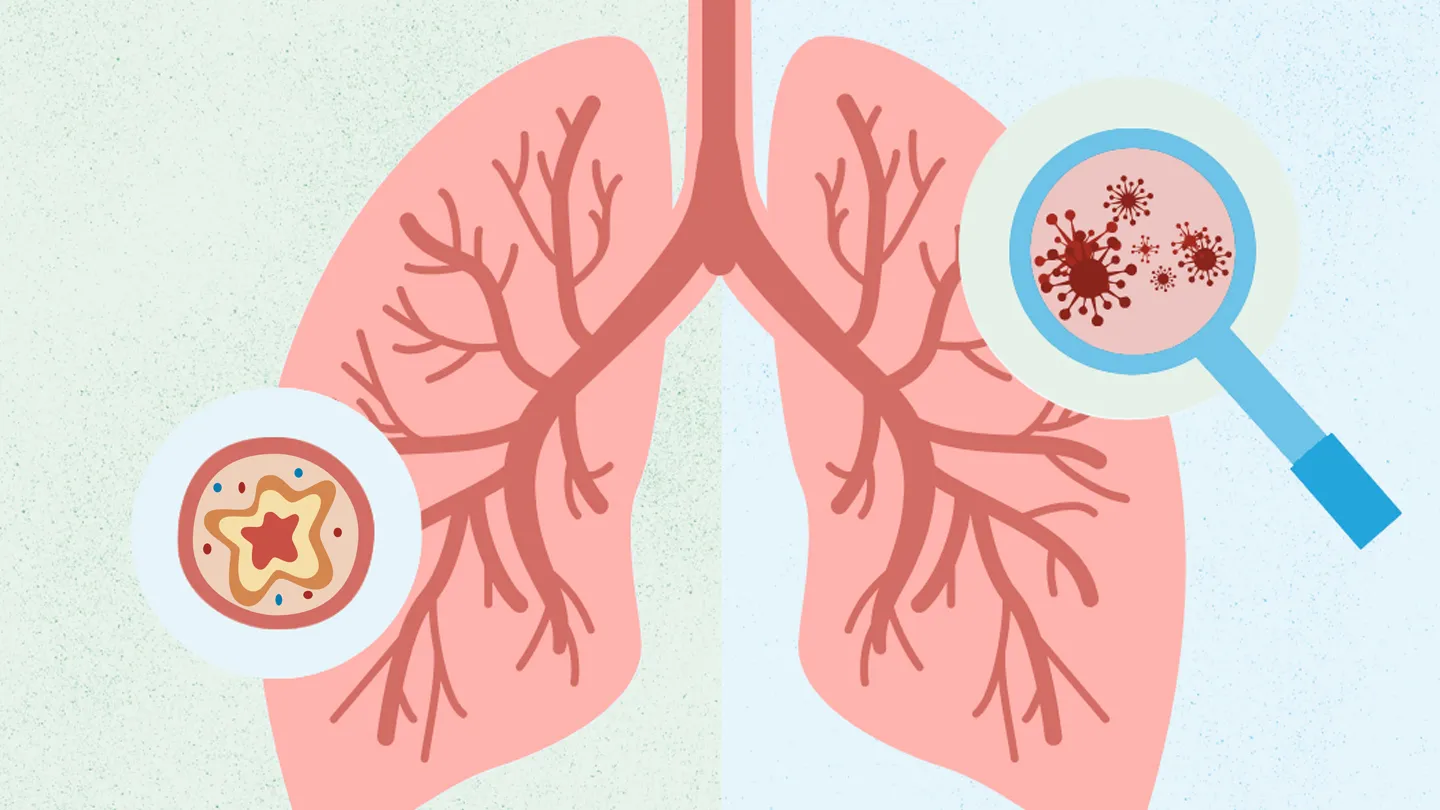

Бронхитис е кога вашите бронхијални цевки, кои носат воздух до вашите бели дробови, се инфицираат и отекуваат.

Пневмонијата е уште една инфекција во вашите бели дробови, но наместо во бронхијалните цевки, ја добивате во ситни воздушни кесички во белите дробови наречени алвеоли. Може да биде благо, но понекогаш сериозно, особено за многу млади, возрасни 65 или постари и луѓе со послаб имунолошки систем.

Во двата случаи, додека вашето тело се бори против бактериите, вашите бронхијални цевки отекуваат и произведуваат повеќе слуз. Тоа значи дека имате помали отвори за проток на воздух, што може да го отежне дишењето.

Додека вашето тело се бори против бактериите, воздушните кеси на белите дробови отекуваат и може да се полнат со течност или гној, слично како што вашите бронхијални цевки отекуваат и се полнат со слуз кога имате бронхит